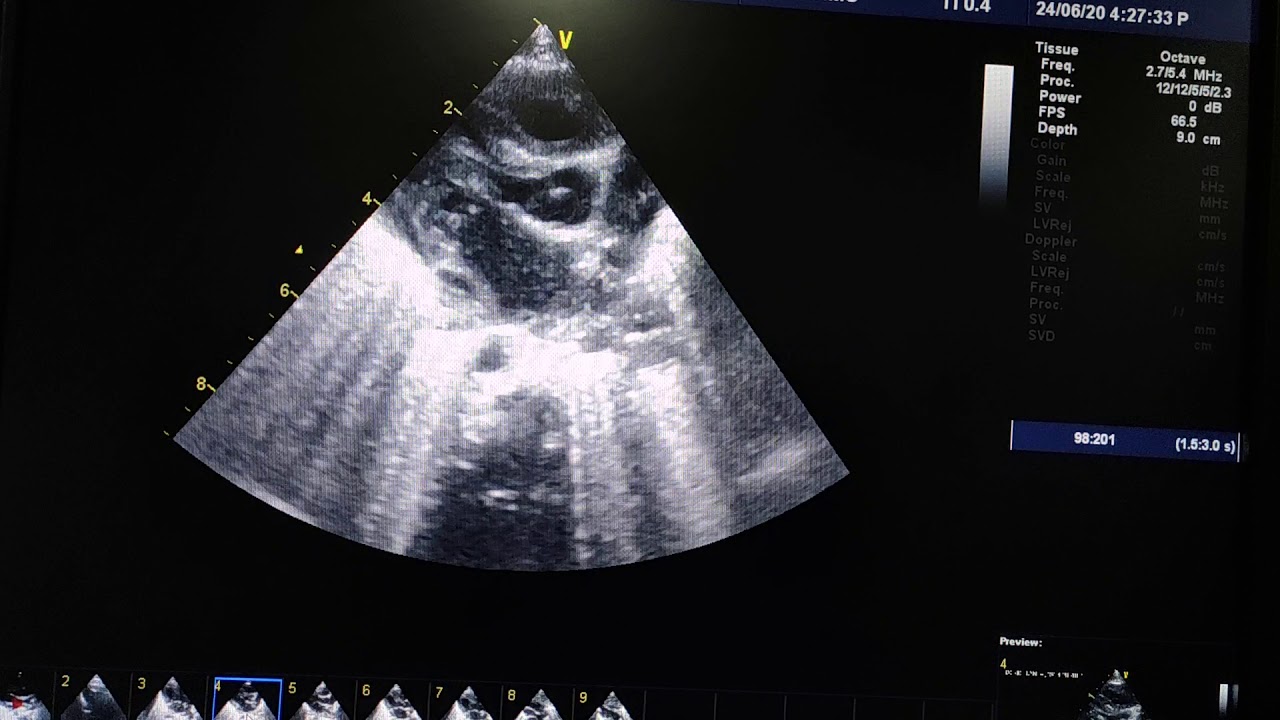

Persistent left superior vena cava - YouTube

If you are seeking video info pertaining to Persistent Left Superior Vena Cava - YouTube keyword phrases, you have actually concerned the appropriate blog site. Our blog site has numerous collections of video clips from the most effective sources relevant to what you are looking for such as Persistent left superior vena cava 2 - YouTube, Persistent Left Superior Vena Cava - YouTube and also Persistent left superior vena cava - YouTube.

Play

Next is a video clip about Persistent left superior vena cava - YouTube which is presently trending and is being sought by numerous netizens, you can play it directly on this web page for inspiration or possibly download and install video clips to be used as video clip collections on your device.